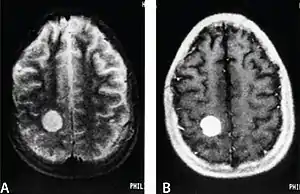

| MRI of a cardiac angiosarcoma that has metastasised to the brain. | |